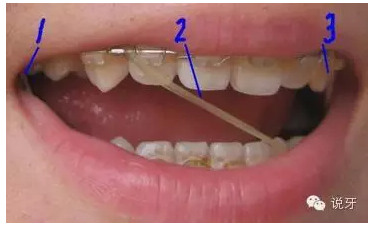

9、上橡皮筋

一般來說,牙齒的排齊會因本身的牙齒移動快慢和醫(yī)生的技術(shù)各方面因素而不同。一般1個月左右能顯現(xiàn)出一些變化,而6個月左右基本排齊。牙齒排齊以后牙縫開始收合,此時需要皮筋的幫忙。需要注意的是皮筋在吃飯時需要摘下來。